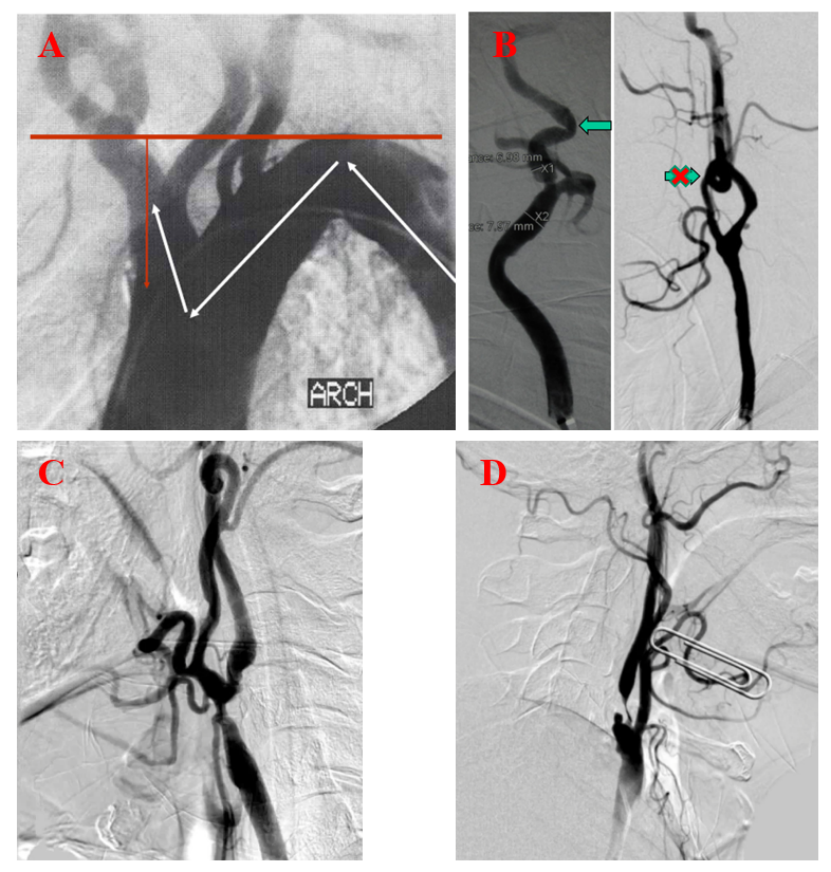

分叉位置:颈动脉分叉过高或过低,影响支架定位与释放。 主动脉弓型:从Ⅰ型弓到Ⅲ型弓,导管到位难度递增,尤其对老年、血管迂曲患者;

颈动脉迂曲:颈总动脉或颈内动脉严重弯曲,导致长鞘、保护装置或支架系统难以到达理想位置;

图:A:困难入路-主动脉弓型;B:困难入路-动脉扭曲;C:病变位置-分叉型;D:病变性质-溃疡型